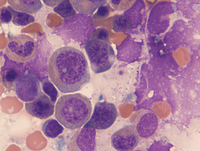

Aspirate smears

On the aspirate smears erythroid maturation is progressive with some atypia/nuclear irregularity and megaloblastoid change. There is no vacuolation in the erythroid precursors (as might be seen with copper deficiency). Myeloid maturation is left shifted with very occasional neutrophils with abnormal chromatin clumping. Lymphoid cells are not significantly increased.